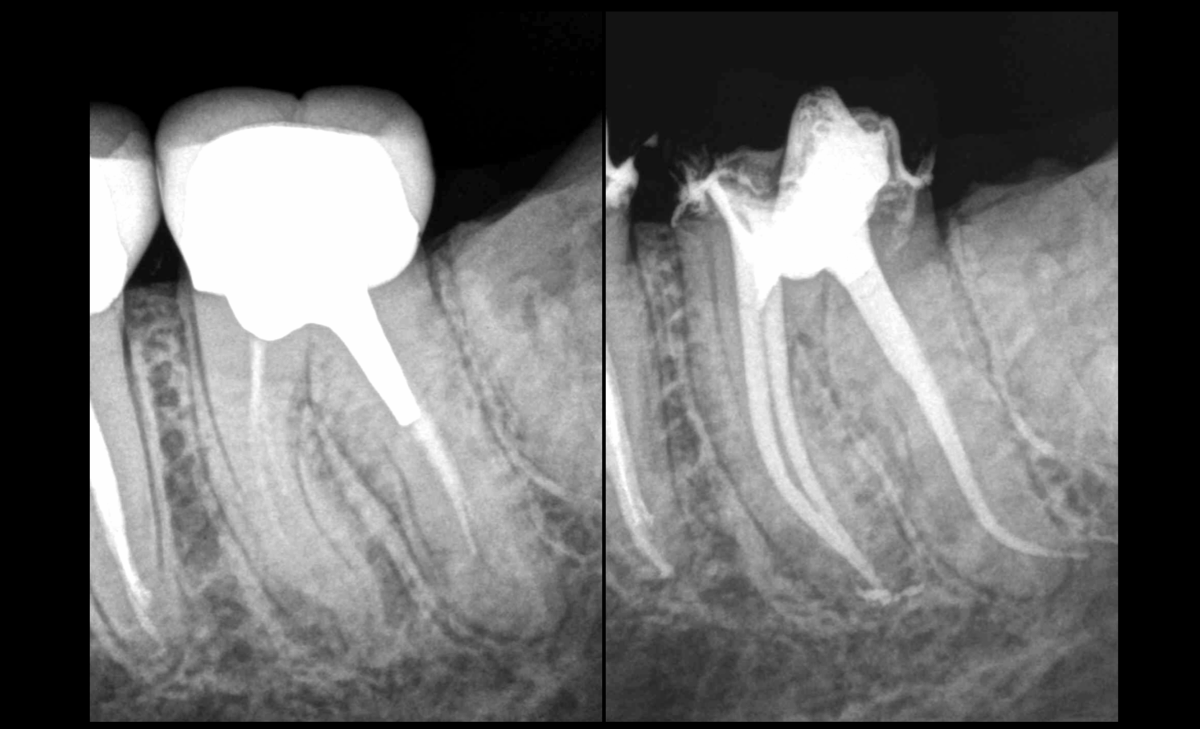

❓Quel facteur pourrait conditionner dans ce cas l’indication de retraitement canalaire ?

🦷 Réponse : la possibilité de reconstruire la dent de façon fiable et pérenne dans le temps

✅ Notre correspondant a déposé la couronne et validé le fait qu’une nouvelle prothèse était bien réalisable.